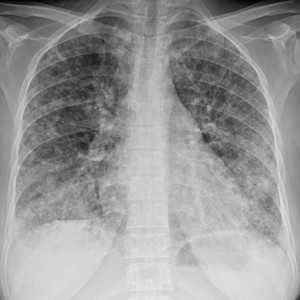

Метастазы в легких — фото рентгенограммы. Округлые тени — метастазы рака пищевода. Хорошо виден большой узел округлой формы вблизи переднего отрезка 2-го ребра. На снимке справа - циркулярное сужение пищевода за счет опухолевого утолщения его слизистой оболочки.